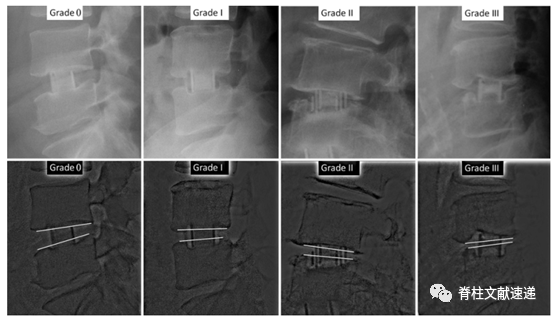

该文献作者通过对比使用两种不同宽度的Cage(18mm和22mm,见下图)以探索Cage宽度对术后Cage下沉的影响,并根据Cage下沉的不同程度将其分为四级(0级、I级、II级、III级,如图所示)。46位患者(共61个节段)使用了前后经为18mm的Cage,28位患者(共37个节段)使用了前后经为22mm的Cage。术后12个月时,30%的18mm组和11%的22mm组出现了II级或III级Cage下沉。

图注:根据侧位X线片,测量Cage下沉到椎体终板内的量将其分为四级:0级(0%-24%);I级(25%-49%);II级(50%-74%);III级(75%-100%)。0、I级为低等级下沉,II、III级为高等级下沉。